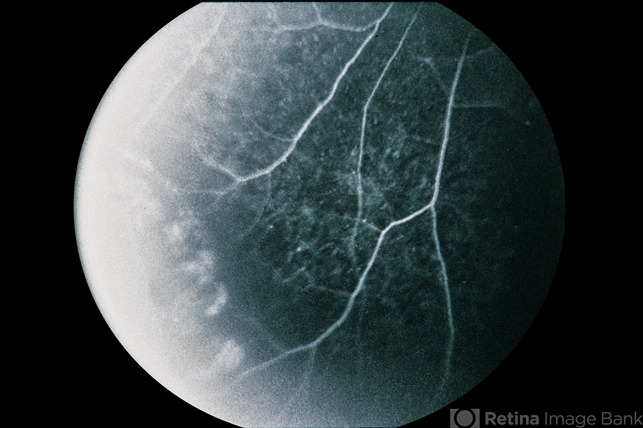

- branch retinal vein occlusion (BRVO), congenital hypertrophy of the retinal pigment epithelium (CHRPE)

- 73-year-old white male, BRVO / CHRPE.